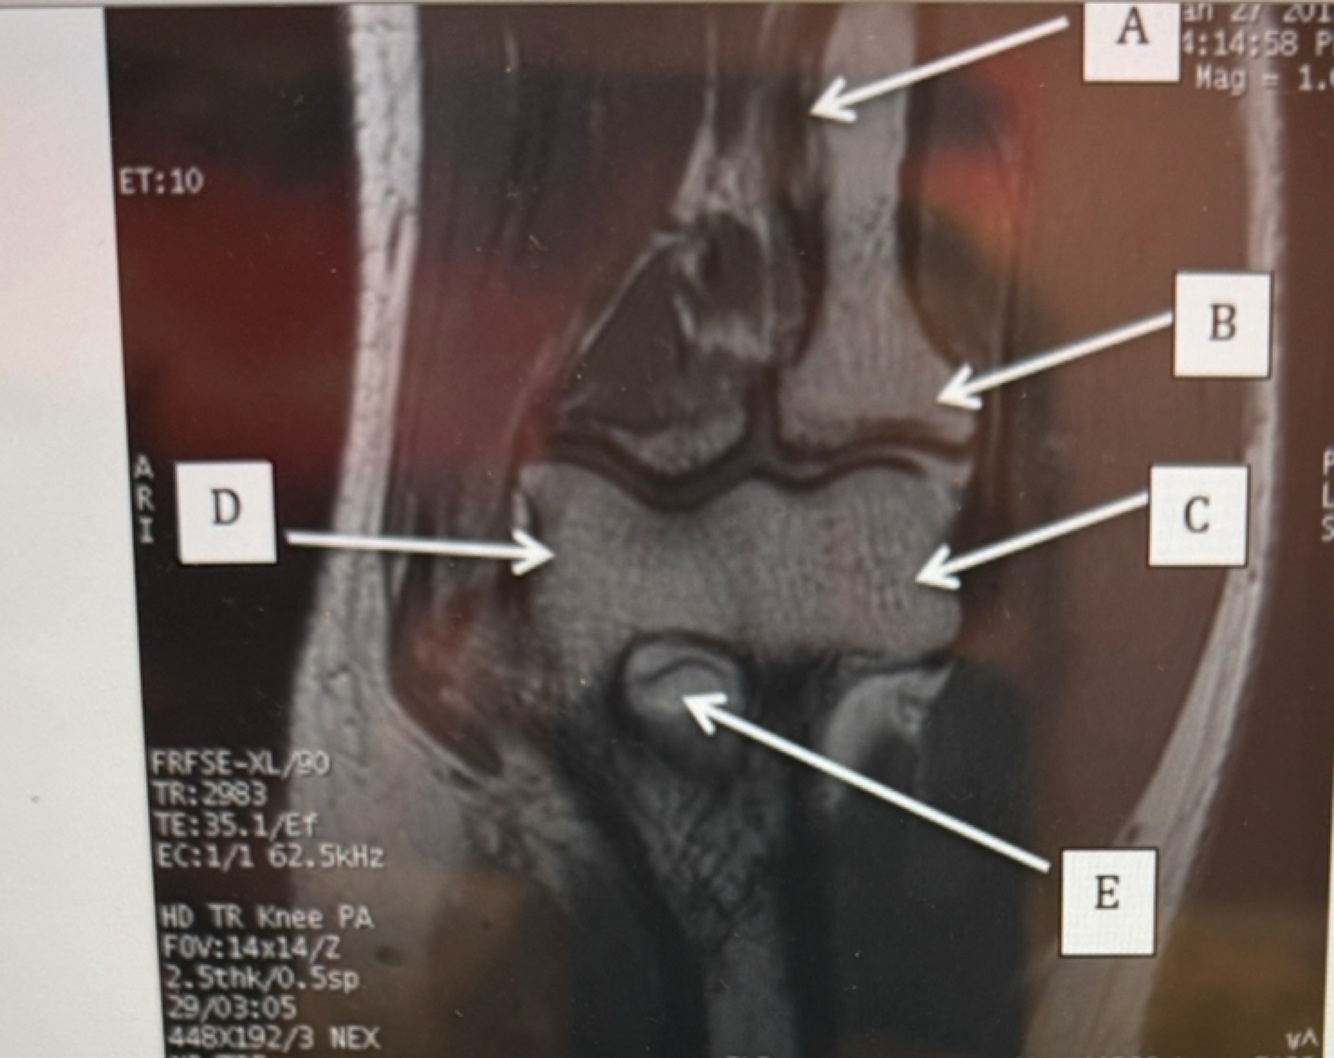

Q

Capitulum

Radial head

Trochlear

A

B radial head

C capitulum

D trochlear